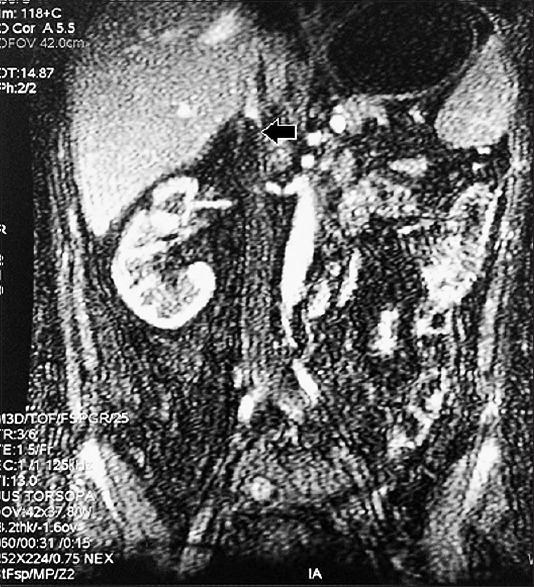

A 46-year-old male presented with left flank pain and was found to have left nephromegaly with renal vein and inferior vena cava (IVC) thrombus. On hematological evaluation, he had leukocytosis and thrombocytopenia. Further evaluation revealed acute myeloid leukemia (AML). Following initial cytoreductive therapy and supportive care for hyperleukocytosis, he underwent left simple nephrectomy with IVC thrombectomy. Postoperatively, he developed massive thrombosis of infrahepatic IVC with renal failure. Renal venous thrombosis as a rare presentation of AML in adults with leukemic hyperleukocytosis has not been reported. In the absence of clear guidelines, early diagnosis and management are desirable.

一名46岁男性因左侧腰痛就诊,检查发现左肾肿大并伴有肾静脉及下腔静脉血栓形成。血液学评估显示他存在白细胞增多和血小板减少。进一步检查发现急性髓系白血病(AML)。在接受初始细胞减灭治疗及针对白细胞增多的支持治疗后,他接受了左肾单纯切除术及下腔静脉血栓切除术。术后,他出现肝下下腔静脉大量血栓形成并伴有肾衰竭。肾静脉血栓形成作为成人白血病性白细胞增多症中AML的一种罕见表现尚未见报道。由于缺乏明确的指导方针,早期诊断和管理很有必要。